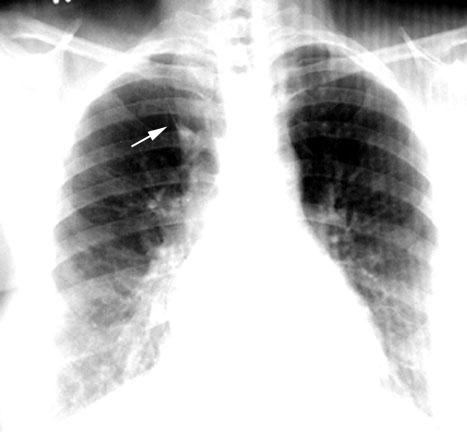

The azygous vein indents the pleura as it joins the SVC. This is not to be mistaken for transverse fissure.

This is an example of an azygous lobe.